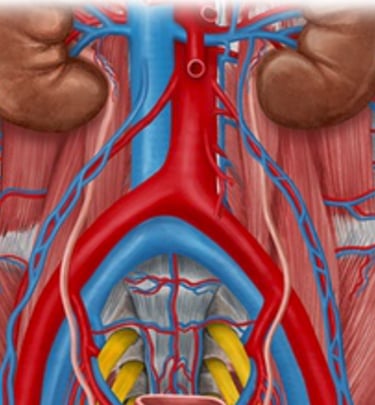

Precision in lumbar spine surgical exposures with prospective data analysis to optimize surgical outcomes

Snapshots of precision in lumbar spine imaging

Precision Imaging